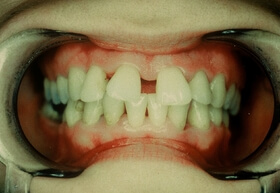

Agresszív fogágybetegség miatt kialakult frontfog elmozdulás – elülső nézet